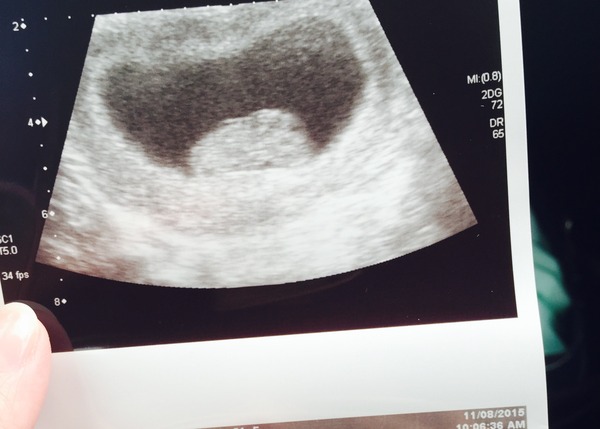

here's my bean from private scan today...in which I was put ahead to 11+1, which is good.

Oh wow maybe that's a wonderful sight,

looks so much more like a baby than my 9+1 scan, baffles me the changes in such a short space of time.

maybebabybee · 19/08/2015 15:40

Q I know, I couldn't believe the change from my 8+4 scan, I thought it looked quite baby-like then but nothing compared to now.

Welcome Tri, that's a nice surprise for you :)

maybe your scan picture is so cute :) I'm scared now because I had my scan at 9+6 and baby looks quiet big so I don't know if my dates are right? we'll find out on Friday I guess haha I swear I could see baby's fingers, looks like baby is sucking it's thumb? what do you girlies think?

rosie that looks about right for 9/10 weeks from pics I've seen :)

Did they give you baby's measurements?

maybe they said they i'm right on dates but on the 28th my 12week scan they'll give me more accurate dates and measurements. I thought baby would be smaller though haha I don't know about you but I can't stop staring at my pic all the time :)